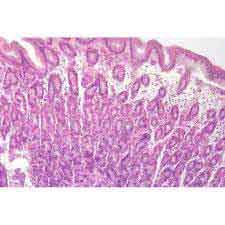

| Description | Liver t.s., Pancreas t.s., Intestine t.s., Lung t.s., Kidney t.s., Testis t.s., Appendix t.s., Oesophagus t.s., Thyroid gland t.s., Stomach t.s., Ovary t.s., Adrenal gland t.s., Kidney l.s., Spleen t.s., Caecum t.s., Rectum t.s., Blood smear, *, Squamous epithelium, Stratified squamous epithelium v.s., Columnar epithelium, Ciliated epithelium, Areolar tissue, Adipose tissue, Hyaline cartilage t.s, Bone ground thin t.s., Bone decalcified t.s., Striated muscle l.s., Cardiac muscle l.s., Non-striated muscle l.s., Nerve t.s., Ovary adult v.s., Artery t.s., Blood smear, Ileum t.s., Ovary with corpus luteum, Spinal cord t.s., Stomach cardiac t.s., Tooth decalcified, Brain cerebrum t.s., Bone calcified t.s., Duodenum t.s., Heart t.s., Jejunum t.s., Larynx t.s., Oviduct t.s., Skin v.s., Tongue t.s., Vein t.s., Brain cerebellum t.s., Epiglottis t.s., Heart l.s., Lung l.s., Lymph gland t.s., Parathyroid gland t.s., Salivary gland, Penis t.s., Stomach fundus t.s., Retina v.s., Tail t.s., Uterus t.s. |

Microscopes Prepared Slides

Mammalia Histology (Rat or Rabbit)